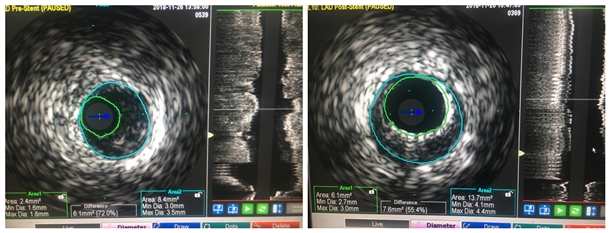

经过详细评估后决定不使用造影剂,为其实行IVUS辅助指导,探查血管内狭窄程度,进行无造影剂冠脉检查。在心内科邓捷主任医师,朱参战副主任医师的指导下,由主管医生王新宏及刘小军主治医师担任术者,李青主治医师,介入技师李晓峰及介入护师段文娜、王军密切配合。手术开始,植入超声探头,显示患者前降支近中段重度狭窄,血管面积仅存2.4mm²,考虑引起杨女士心前区疼痛应该是此血管。简短术式讨论后,继续在IVUS 指导下进行支架植入术,成功为前降支植入支架两枚。全程患者无不适及并发症,生命体征平稳。